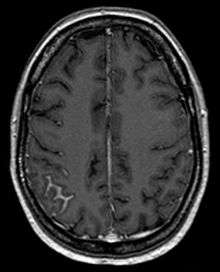

Meningeal carcinomatosis in a patient with breast cancer (contrast-enhanced axial T1-weighted MRI)

Meningeal carcinomatosis is a condition in which a solid tumor diffusely spreads to the leptomeninges. Lung tumors, breast tumors, and malignant melanoma comprise the majority of solid tumors spreading to the leptomeninges.